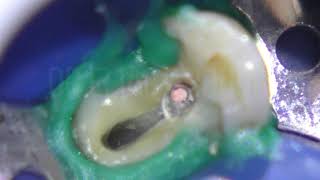

Warm Vertical Compaction Technique From Sectional...

108.929

3:20

Abboud - Warm Vertical Compaction Technique 1

2.241

1:09

Warm Vertical Compaction

198

5:12

Warm Vertical Compaction, Apical Scouting Apical...

508

1:23

Endodontics Obturation Techniques Warm Vertical...

89.167

6:54

Master Warm Vertical Condensation In Just 6...

2.681

6:43

Vertical Condensation

3.762

3:01

Video 4 Warm Vertical Condensation For Obturation

637

2:00

Warm Vertical Condensation Wdr. Herbert Schilder

0:47

Warm Vertical Compaction Eqv Wide C Of Maxillary...

364

1:40